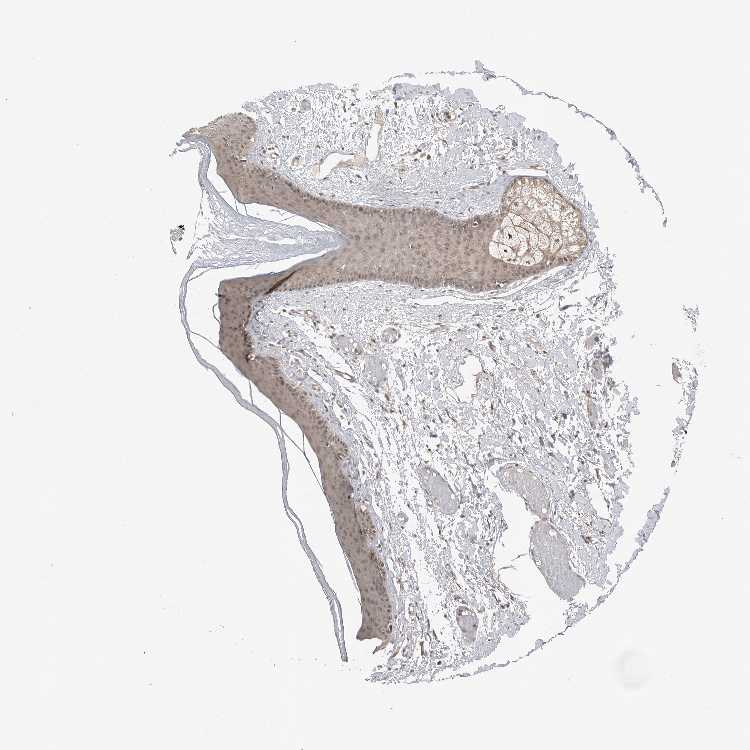

SKIN 1 - Antibody stainingi

Antibody staining in the annotated cell types in the current human tissue is reported as not detected, low, medium, or high, based on conventional immunohistochemistry profiling in selected tissues. This score is based on the combination of the staining intensity and fraction of stained cells.

Each image is clickable and will lead to virtual microscopy that enables deeper exploration of all samples and also displays staining intensity scores, fraction scores and subcellular localization as well as patient and tissue information for each sample.

Antibody HPA024823

Langerhans Low

Fibroblasts Not detected

Keratinocytes Medium

Melanocytes Low